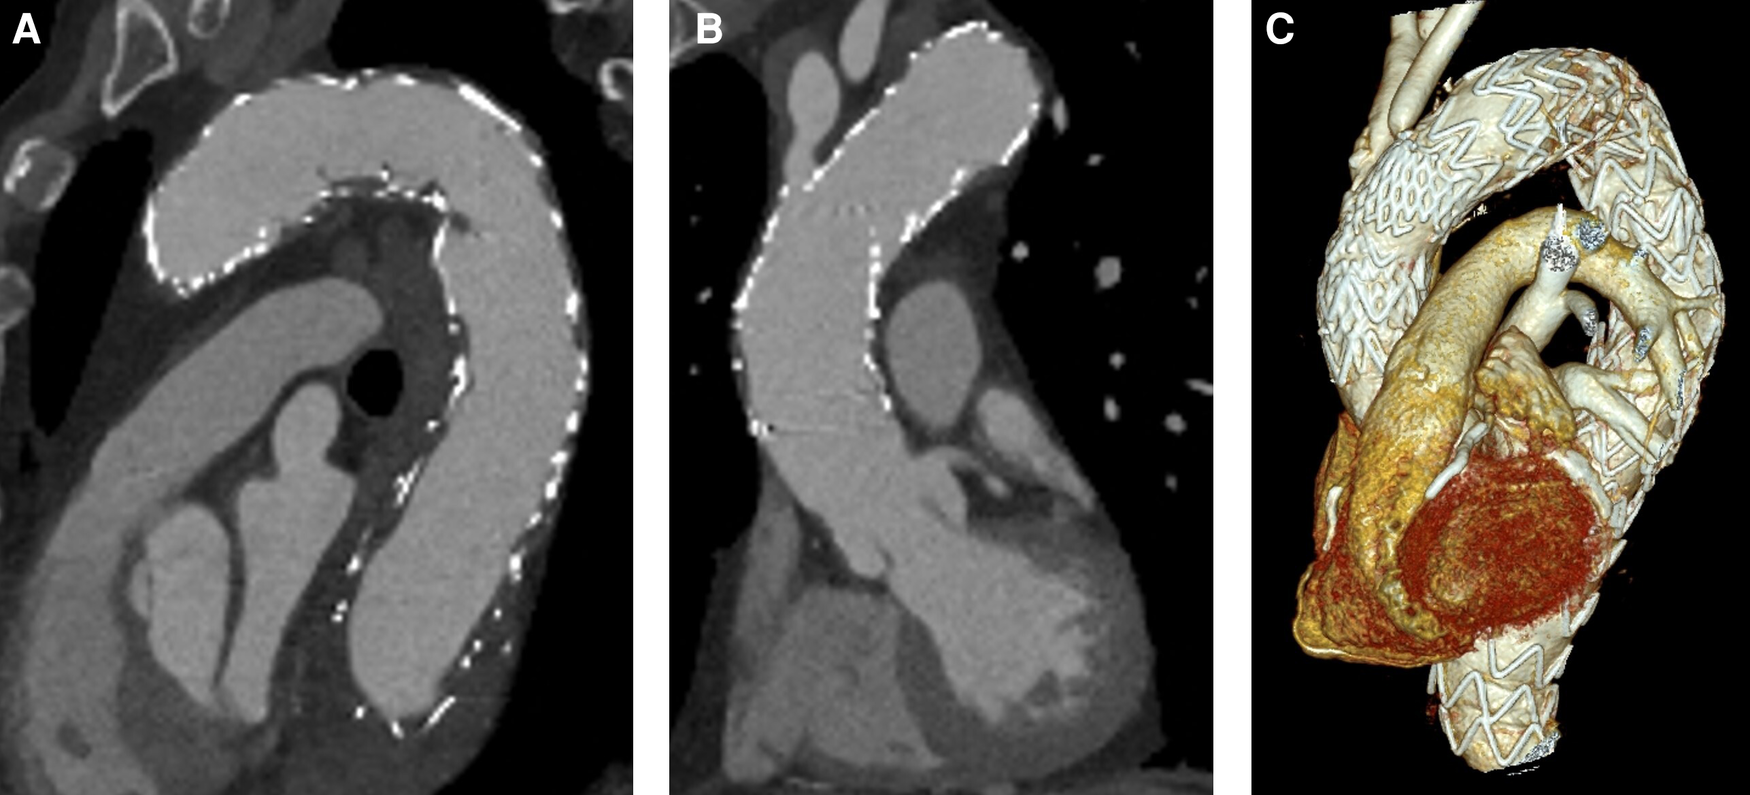

Figure 4

Postoperative CTA. (A) Stent grafts covering the ascending aorta and the aortic arch with no patent false lumen. (B) No residual dissection in the ascending aorta. (C) 3D reconstruction.

The patient was transferred to the intensive care unit under stable conditions. Due to slight anisocoria and still cold and pale right leg, CTA was performed. No signs of cerebral ischemia or vessel obliteration were evident. Right femoral and iliac artery was dissected, but distal perfusion was preserved and peripheral pulses were palpable. Symptoms diminished in the further course and the patient was extubated after the first postoperative day. However, he initially presented with paraparesis with only minimal preserved motoric function of the right leg. Fortunately, motoric function recovered significantly in the further course. No signs of endoleak or false lumen patency could be detected by CTA. Results of postoperative CTA (SOMATOM Definition Flash, Siemens®, Erlangen, Germany) is shown in Figure 4. The patient was referred to the normal ward on the eighth postoperative day after slowly recovering from postoperative delirium.

No aortic re-interventions were necessary after discharge. After 3.5 years of follow-up, CTA showed no progress of the disease, including no evidence of stent failure, no signs of endoleak, and no aneurysm or dissection progress. CTA (SOMATOM Definition Flash, Siemens®, Erlangen, Germany) results are shown in Appendix Figure A1. A timeline that summarizes the patient's course including the relevant events is shown in Appendix Figure A2.

Figure A1

CTA follow-up 3.5 years later. (A) No endoleak in the aortic arch. (B) No disease progress in the ascending aorta. (C) 3D reconstruction.